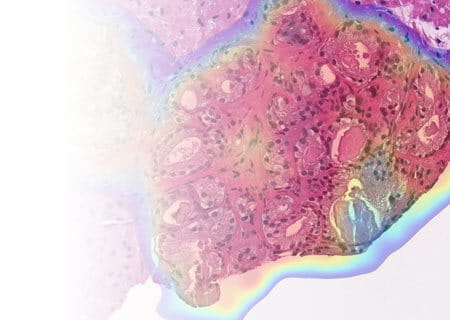

New Option for Recurrent Breast Cancer

Our team led a prospective study to demonstrate that women may be able to avoid mastectomy for recurrent breast cancer and instead use a far less morbid radiotherapy treatment with partial breast IORT. Read Study Results